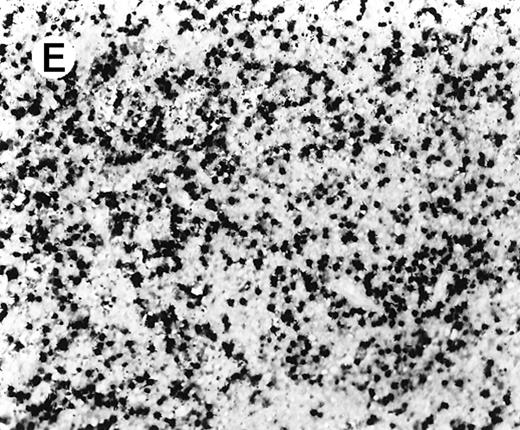

Staining for CD4 and CD8 in spleen from case 2.

(A) The lymphoid infiltrate in the spleen is predominantly CD8+. (B) Staining for CD4 highlights erythrophagocytic histiocytes, whereas the lymphocytes are negative. (C) The small lymphocytes express TIA-1. (D) They are BF1+ and are strongly EBER-1+ (E) (immunoperoxidase stained, hematoxylin counterstained, × 200).